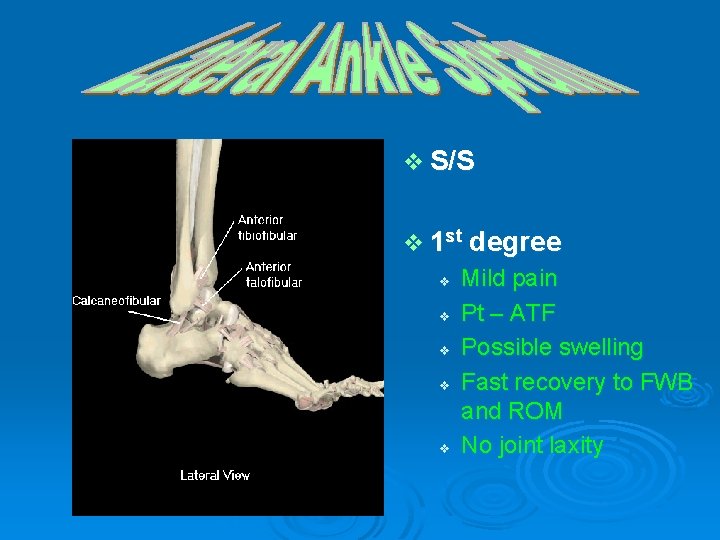

v S/S v 1 st v v v degree Mild pain Pt – ATF Possible swelling Fast recovery to FWB and ROM No joint laxity